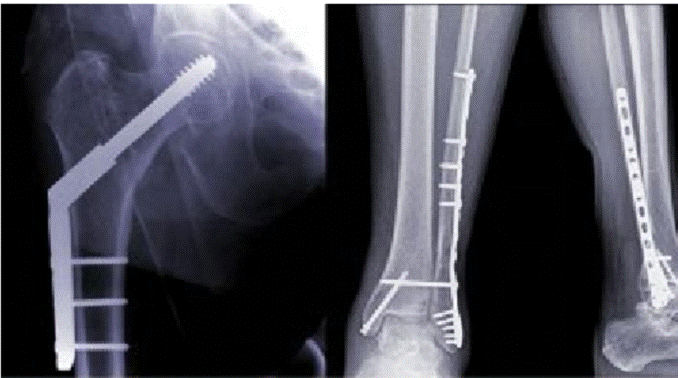

1.Biomedical functional materials, committed to the research and development of bone filling materials, orthopedic implant surface modification, bone biomechanics and molecular research.